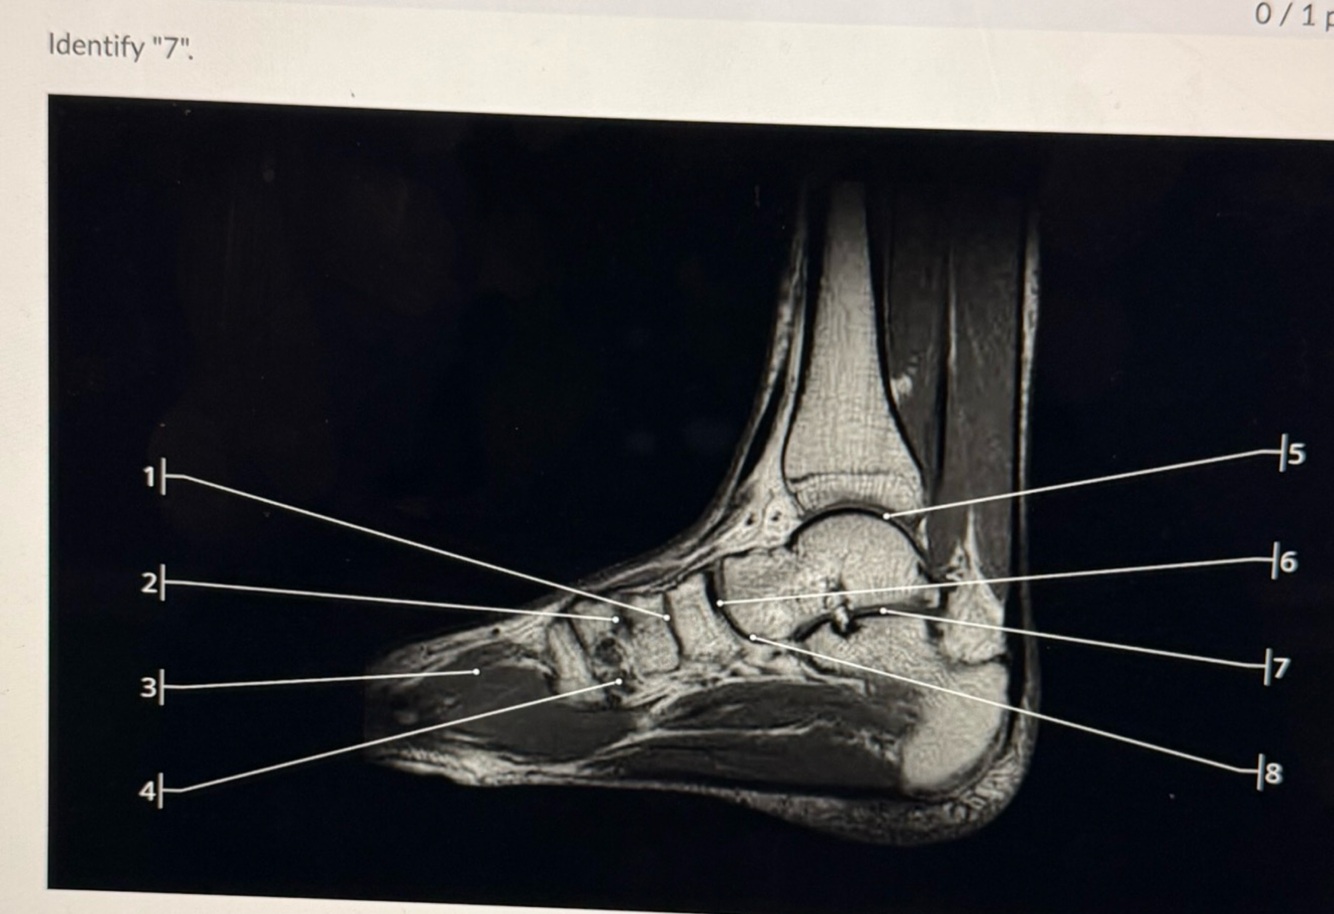

5

Q

A

Posterior subtalar joint